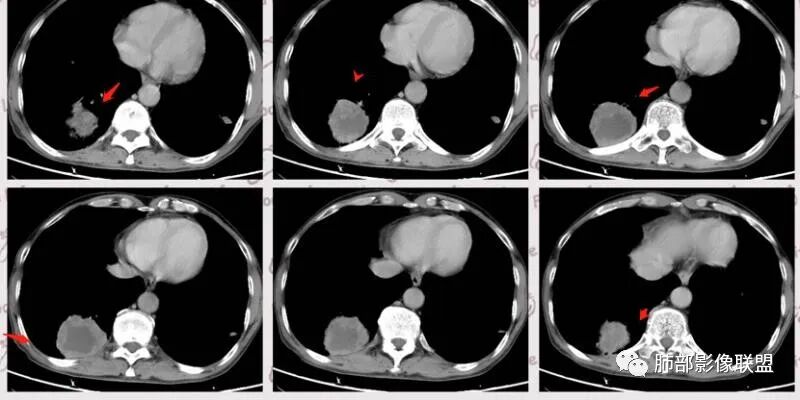

老年男性,肺气肿背景,结核病史。右肺下叶病灶,分叶不明显,局部可疑栽赃,毛刺略呈毛刷感,远端阻塞性肺炎改变,轻微强化,走行血管僵硬,湖泊样坏死,考虑鳞癌。左肺病灶边缘有分叶、毛刺及胸膜牵拉的恶性征象,也有平直收缩的良性征象,可疑卫星灶,这类良恶征象都有判断比较纠结,常规思路:炎性放前边,腺癌待排。

临床病史很长,背痛9年可能与左侧胸膜炎有关。两上肺陈旧性结核伴肺气肿没有问题。左下肺病灶,分叶毛刺、胸膜凹陷、指状凸起,增强轻度强化,腺癌问题不大。右侧附加题有些困难,病灶内血管显影,不像结核的表现,先把结核否掉?鳞癌和慢性脓肿的鉴别:支持良性的征像,低密度区内也有细小血管影,不像鳞癌坏死?与胸膜关系整体还是比较和谐,边缘还算光整,毛刺都在远端,不支持慢性脓肿的的地方,周围支气管管壁都很干净。恶性征像,与支气管的关系图片给的不够。坏死边缘不光整,有些浅分叶。总体,我觉得坏死区血管的存在更有价值,验证一下,右侧首先考虑慢性脓肿。

患者老年男性,因咳嗽 咳痰 背痛就诊。既往有喉及肺结核病史。胸部CT:左下肺实性病灶,边缘可见短硬毛刺,分叶,胸膜牵拉,增强可见强化,考虑肺腺癌。

右下肺实性病灶,进入病灶支气管阻塞,支气管壁增厚,病灶内可见坏死,内壁凸凹不平,增强可见病灶强化,考虑恶性病变,鳞癌?

老年男性,结核、慢性病史,肺气肿背景,右肺胸膜下肿块影,边界清晰,边缘膨隆,中度环形强化,内见边界清晰坏死区,并见部分强化小血管,鳞癌破坏力强,而且病灶一侧支气管受推移,首先考虑右肺结核,鉴别鳞癌,左肺考虑腺癌,胸膜牵拉,膨隆生长,边缘毛刺样,潜在分叶。

老年男性,既往肺结核病史。肺气肿背景,可见钙化灶及条索影。右肺下叶胸膜类圆形占位,边界清晰,内部可见边界清晰的坏死区,轻度强化,考虑为结核可能;左肺下叶结节,可见分叶,毛刺,胸膜牵拉,增强可见强化,考虑为恶性,腺癌可能。

左肺肺气肿,双肺多发结节,上肺多发纤维索条影及钙化,符合陈旧性结核病变。右肺下叶结块,边缘毛糙,内部可见低密度坏死,环形强化,坏死边界清楚,考虑脓肿,OP。左肺下叶结节,边缘可见毛刺,深分叶,边缘收缩,远端牵拉胸膜,考虑肺癌,腺癌。

老年男性,肺气肿背景,左肺下叶结节,深分叶,毛刺,胸膜牵拉,内部可见坏死,坏死边界不清,不均匀强化。右肺下叶大肿块,边缘有毛刺,多发小灶性坏死,胸膜下有侵犯,考虑恶性,左肺下叶腺癌,右肺下叶低分化鳞癌。

男,64岁,咳嗽咳痰,气喘10余年,右肺下叶软组织密度肿块影,边界清晰,边缘见细短毛刺及分叶,轻度胸膜粘连,病灶内密度不均,增强扫描看见坏死区,病灶边缘明显强化,考虑鳞癌可能。左肺下叶病灶深分叶、毛刺、胸膜牵拉,考虑腺癌可能,除外转移性病变。

双肺陈旧性肺结核,肺气肿背景。右肺下叶肿块,边缘毛糙,内部可见大片低密度坏死,环形强化,坏死边界清楚,考虑鳞癌。左肺下叶结节,边缘可见毛刺,深分叶,有收缩,有膨隆,胸膜牵拉,考虑腺癌。

双侧恶性肿瘤应该没有问题,右肺的话,坏死明显,壁光滑,肉瘤样癌,鳞癌,低分化腺或粘液腺。

1.左侧分叶深一些

2.右侧糊墙

左侧胸膜凹陷

3.左侧支气管显示欠佳,似乎在门口堵塞

右侧支气管门口堵塞,有推移迹象

4.右侧坏死明显,内部囊变坏死边缘部分清楚、部分不清

左侧坏死不明显

主要征象:病灶分叶不明显、较光整,局部胸膜栽赃,支气管门口堵塞,有推移迹象;增强后坏死明显,内部囊变坏死边缘部分清楚、部分不清楚,病灶内可见血管,局部稍毛糙,实性部分强化较明显,总体考虑恶性病变。一部分征象指向鳞癌(支气管截断、坏死较多,病灶内血管破坏),但又有肉瘤的一些特点(病灶较大,缺乏分叶,坏死边界清晰),要考虑到肉瘤样癌。